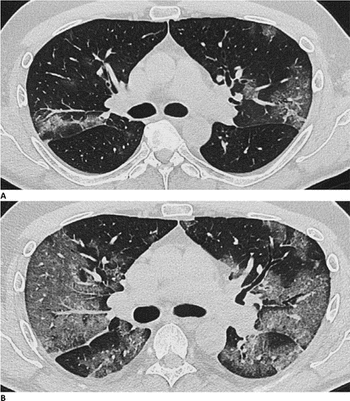

COVID-19 and Long-Term Lung Effects; Reduce Emergency Department Imaging Recalls; COVID-19, Myocarditis, and Athletes; Plus, New Recommendation for X-ray Gonad Shielding

CT and heart attack prediction; lagging outpatient imaging volume recovery; equivalent thoracic MRI performance with COVID-19 pneumonia; and CT colonography during COVID-19

Scans show cardiovascular impact lingers after the acute phase of viral infection and into recovery.